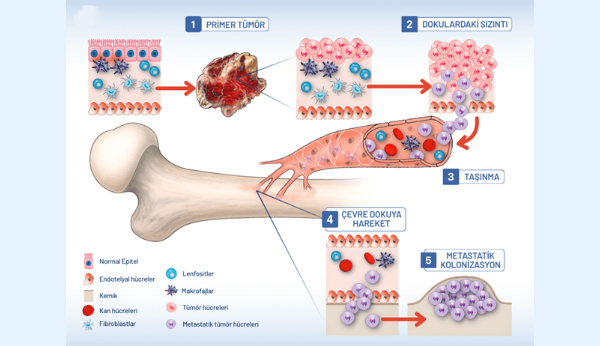

سرطان استخوان ثانویه (متاستاتیک)

سرطان استخوان ثانویه یا متاستاتیک زمانی رخ میدهد که سلولهای سرطانی از قسمت دیگری از بدن مانند سینه، ریه یا پروستات، به استخوانها گسترش مییابند. سلولهای سرطانی پس از استقرار در استخوان، روند بازسازی استخوان را مختل میکنند و نقاط ضعیف یا نواحی غیرطبیعی متراکم اما شکننده ایجاد میکنند.

خرابی ساختاری حاصل میتواند باعث درد استخوان شود و شکستگی ناگهانی در استخوان ضعیف شده میتواند درد را تشدید کند.